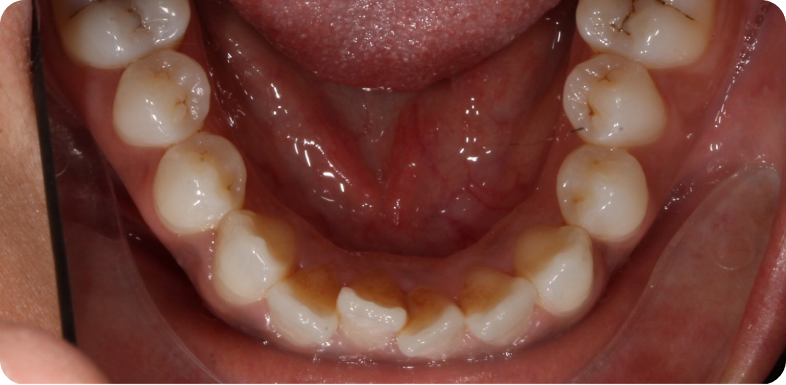

- des fils de contention collés sur la face interne des incisives et canines, à la mandibule et au maxillaire lorsque cela est possible, à conserver le plus longtemps possible ;

Cas cliniques